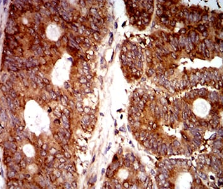

EIF5 Mouse Monoclonal antibody[6D6H]

Immunogen:    Purified recombinant fragment of human EIF5 (AA: 1-300) expressed in E. Coli.

IHC    1/200 - 1/1000